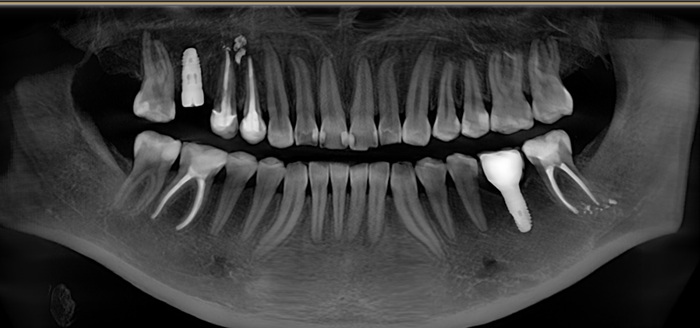

В январе 2018 молодой девушке была проведена имлантация в области 6го зуба на нижней челюсти слева, а коронка установлена в другом месте.

Ниже фрагмент компьютерной томографии, а интересующий имплантат справа снизу:

Для полной интеграции имплантата необходимо около 4х месяцев, но девушка пришла спустя 6, в июне 2018:

Жалоб нет, имплантат интегрирован. Следующим этом было снятие слепков и изготовление коронки. Ниже снимок от августа 2018:

Казалось, что все в порядке. Так, собственно, оно и было. Контрольный снимок в декабре 2019: